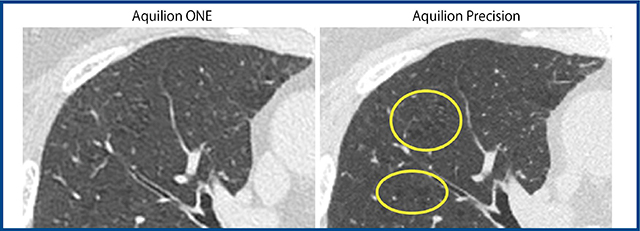

図4 Aquilion Precisionと従来機の胸部CTの違い(同一患者,共に1mm厚)

Aquilion Precisionでは従来機では不鮮明な小葉中心性肺気腫が明瞭に描出される。

図5 5mm厚画像でのAquilion Precisionの描出能(同一患者,共に5mm厚)

Aquilion Precisionでは微細な結節影や網状影が「ぼけることなく」描出される。

Aquilion Precisionで胸部を撮影すると,従来のCTスキャナの画像に比して際立った違いを感じることができる。個人的な感想として,SHRモードまたはHRモードで撮影した場合,(1) 512マトリックスであっても,1mm厚のHRCTは従来CTスキャナの画像に比して「きれい」である,(2) ルーチンで使用される5mm厚の画像(512マトリックス)でも微細構造物の視認性が大幅に向上している,(3) 最高の空間分解能を有する,0.25mm厚・1024(または2048)マトリックスの画像は従来のCTとまったく違う世界を画像診断医に提示する,点が重要ではないかと思う。これらAquilion Precisionの特長は,突き詰めるとXYZ3方向共に0.25mmの検出器サイズであることにすべて由来する。まず,PACSに送りやすい,512マトリックスの1mm厚のHRCTであるが,従来機に比べてノイズや肺野辺縁部のアンダーシュートが改善されており,軽微な肺気腫や間質性肺炎が視認しやすくなっている(図4)。また,臨床の現場で最も頻用される512マトリックス・5mm厚の画像であるが,こちらも胸膜直下まで「くっきりとした」画質を提供できており,従来であれば5mm厚画像ではpartial volume effectなどで「ぼける」はずの微細な結節影などが,かなり明瞭に視認できる(図5)。